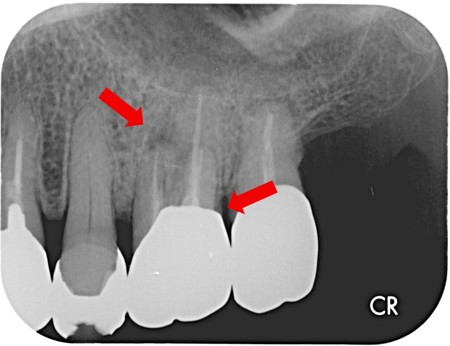

治療前

銀歯の縁の部分が欠けています。 |

昔、虫歯治療を行い神経を取った歯になります。 |